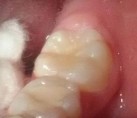

Bệnh nhân: Trần Gia K. 8 tuổi, nam, mã BA 8233/17

Sau ba tháng. ICDAS:2; Di: 21 | Sau sáu tháng. ICDAS:1; Di: 17 | Sau 18 tháng. ICDAS:0; Di: 05 |